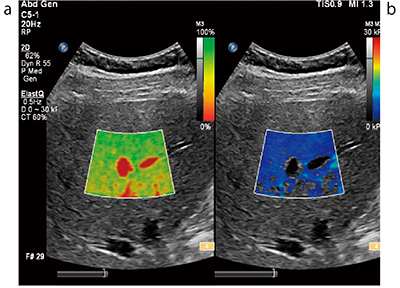

■エラストグラフィの最新技術:ElastQ

フィリップスのエラストグラフィ機能“ElastPQ/ElastQ”は,2018年10月より保険適用となった。ElastQイメージングの特長は,大きなROI(最大5cm×6cm),優れた透過性(単結晶プローブおよび“nSIGHT”技術),データの安定性(データの信頼度を表すConfidence Map)である。世界超音波医学学術連合(WFUMB)の2018年ガイドラインにも,「測定精度を評価できるパラメータを用いた場合,3〜5回の測定が適当である」と新たな記載が追加された。Confidence Map(図2 a)のような精度を評価できるパラメータが同時に参照できることで,安定したデータを再現性良く計測することが可能になる。

図2 ElastQ Confidence Map(a)とStiffness Map(b)